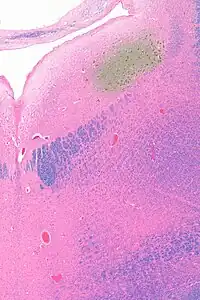

![]() Micrograph showing the locus coeruleus. HE-LFB stain. | |

Anatomy

The locus coeruleus (LC) is located in the posterior area of the rostral pons in the lateral floor of the fourth ventricle. It is composed of mostly medium-size neurons. Melanin granules inside the neurons of the LC contribute to its blue colour. Thus, it is also known as the nucleus pigmentosus pontis, meaning "heavily pigmented nucleus of the pons." The neuromelanin is formed by the polymerization of norepinephrine and is analogous to the black dopamine-based neuromelanin in the substantia nigra.

In adult humans (19-78) the locus coeruleus has 22,000 to 51,000 total pigmented neurons that range in size between 31,000 and 60,000 μm3.[4]